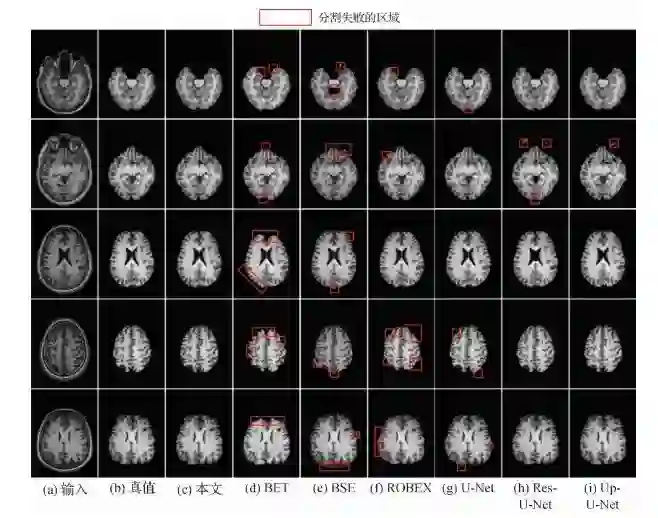

图  不同方法的脑部磁共振图像颅骨去除效果对比

题目:深度迭代融合的脑部磁共振图像颅骨去除网络

作者:姚发展, 李智, 王丽会, 程欣宇, 张健

第一单位:贵州大学计算机科学与技术学院智能医学影像分析与精准诊断重点实验室

引用格式姚发展, 李智, 王丽会, 程欣宇, 张健. 2020. 深度迭代融合的脑部磁共振图像颅骨去除网络. 中国图象图形学报, 25(10): 2171-2181. [DOI: 10.11834/jig.200218]